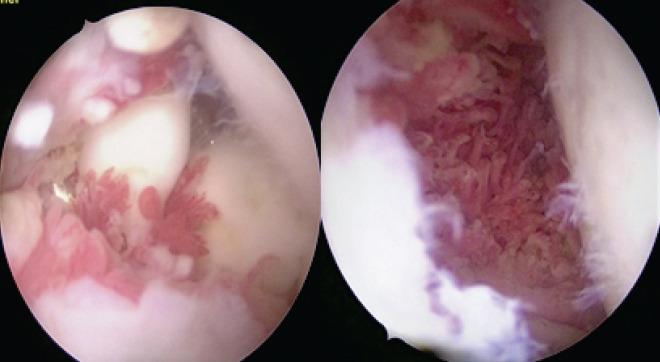

Here, we report a rare case of synovial chondromatosis affecting the right shoulder joint in a 23-year-old male with a 5-year disease duration who presented with progressive pain and restriction in movements which were impacting his routine activities. The loose bodies were removed using the arthroscopic approach combined with a partial synovectomy, and intra-articular methylprednisolone post procedure. The patient showed an excellent recovery in joint mobility within 4 weeks post-operatively, and there were no clinical signs of recurrence during a 6-month follow-up period.

We believe that arthroscopic surgery is effective in the treatment of patients with synovial chondromatosis with advantages such as good visualization, lesser morbidity, and early return of functional activities.

在此,我们报告一例罕见的滑膜软骨瘤病病例,该病例发生在一名23岁男性的右肩关节,病程为5年,患者出现进行性疼痛和活动受限,影响其日常活动。采用关节镜手术联合部分滑膜切除术取出游离体,并在术后关节腔内注射甲基强的松龙。患者术后4周内关节活动度恢复良好,在6个月的随访期内无复发的临床迹象。

我们认为关节镜手术治疗滑膜软骨瘤病患者有效,具有视野清晰、发病率低、功能活动恢复早等优点。